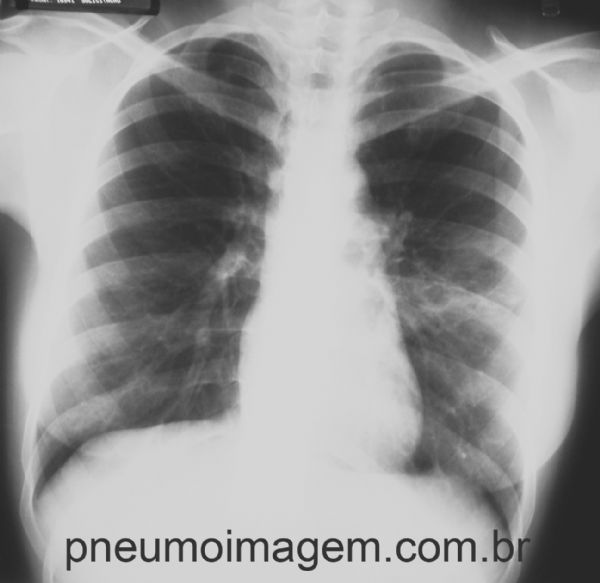

PNEUMONIA EM LÍNGULA

Pneumonia comunitária levando a opacidade em língula. Observe que há perda do contorno da sombra cardíaca à esquerda.

O seio costofrênico está livre, indicando ausência de derrame pleural. Chaves: Pneumonia Adquirida na Comunidade (PAC); pneumonia típica.

Community-acquired pneumonia (CAP) leading to opacity in the lingula. Note that there is blurring of the cardiac shadow on the left.

The costophrenic angle is clear, indicating the absence of pleural effusion. Keys: community pneumonia; lingular pneumonia; typical pneumonia.